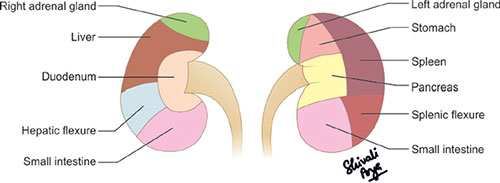

Relations of the Kidneys

The right kidney is related anteriorly with the inferior surface of the liver and the second part of the duodenum while the anterior relations of the left kidney are the pancreatic tail, the spleen, the stomach, the small bowel, the splenic flexure, and the left colon (Fig. 3).4 Posteriorly, the diaphragm, psoas muscle, aponeurosis of the transverses abdominis muscle, and the lumbar muscles are related to the kidneys. Both the kidneys are related superiorly with the adrenal glands while inferiorly the hepatorenal pouch/Morrison's pouch separates the right kidney from the inferior surface of the liver.